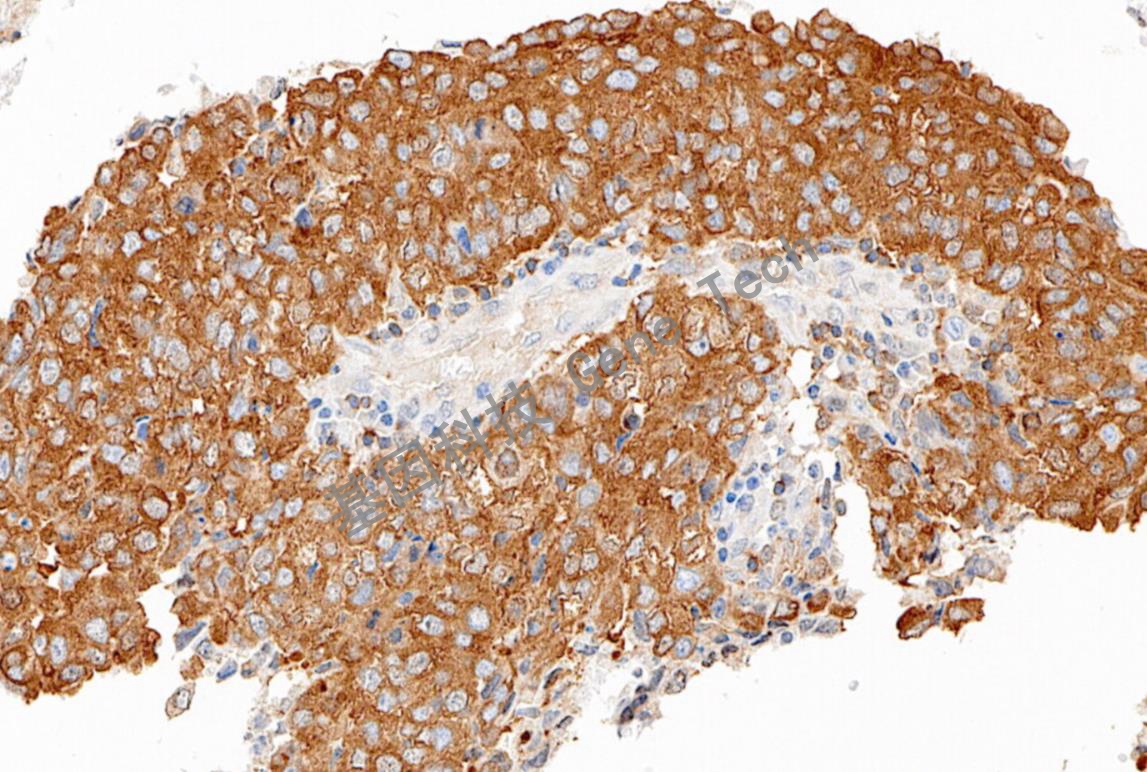

NF Kappa B/p50 鼠抗人 NF Kappa B/p50 抗体试剂(免疫组织化学)

| 预处理:高pH热修复 | 阳性部位:细胞浆 | 阳性对照:胃癌/阑尾 |

| 鳞状细胞癌石蜡切片,用 NF Kappa B/p50(GT2384)染色,细胞浆阳性,DAB 显色。 | ||